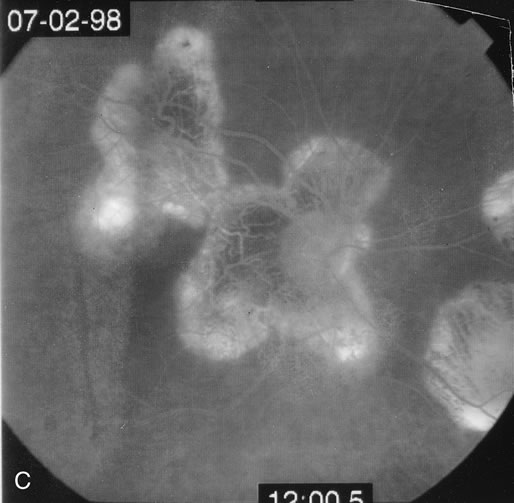

The chorioretinal lesions seen in PIC tend to be small and acutely no larger than 500 μm. They are yellow-whitish and they become atrophic punched out scars. The lesions can also coalesce. Approximately 40% develop choroidal neovascular membranes.40 Fluorescein angiography shows early hyperfluorescence with mild leakage in the later phases.65 There may be increased leakage at the edge in cases of choroidal neovascularization. ICG angiography shows hypofluorescence in the area of the lesions.66 Occasionally there may be some hyperfluorescent spots as well (Figs. 14 and 15).

Fig. 14. A. Right fundus photograph in a patient with multifocal choroiditis showing the small patches of choroiditis. Many have coalesced to form a larger patch. B. Left fundus photograph showing less involvement. C. Indocyanine green angiogram of the fundus shown in Figure 14a showing multiple hypofluorescent spots.

Fig. 15. A. Right fundus photograph of a patient with punctate inner choroidopathy showing the presence of a choroidal neovascular membrane. B. Fluorescein angiogram of the right eye demonstrating the presence of the choroidal neovascular membrane and perpipapillary window defect. C. Left fundus photograph showing large coalesced spots of inactive choroiditis. D. Fluorescein angiogram of the left eye showing staining of the areas of inactive choroiditis. Note the small areas of fluorescence that could not be seen by color photography.